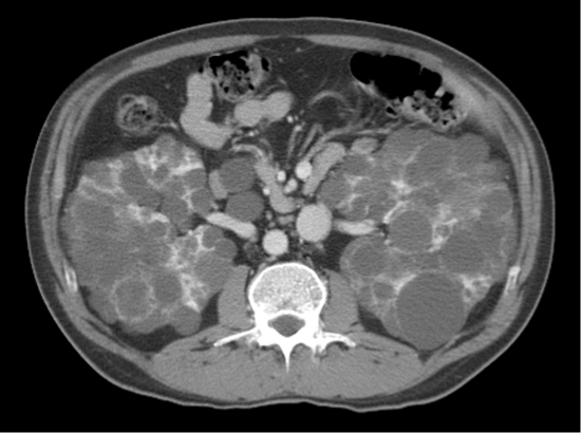

45 year old African American female presents to office with blood in her urine. She has no significant past medical history. Family history reveals sarcoidosis in her mother. Vital signs reveal BP 155/90. Lab studies reveal proteinuria (2.4 g protein), positive anti-double stranded DNA antibodies, and low complement C3 and C4 levels. An US-guided biopsy was performed. A tissue section representative of the remaining tissue is shown in the exhibit. The most likely diagnosis is: